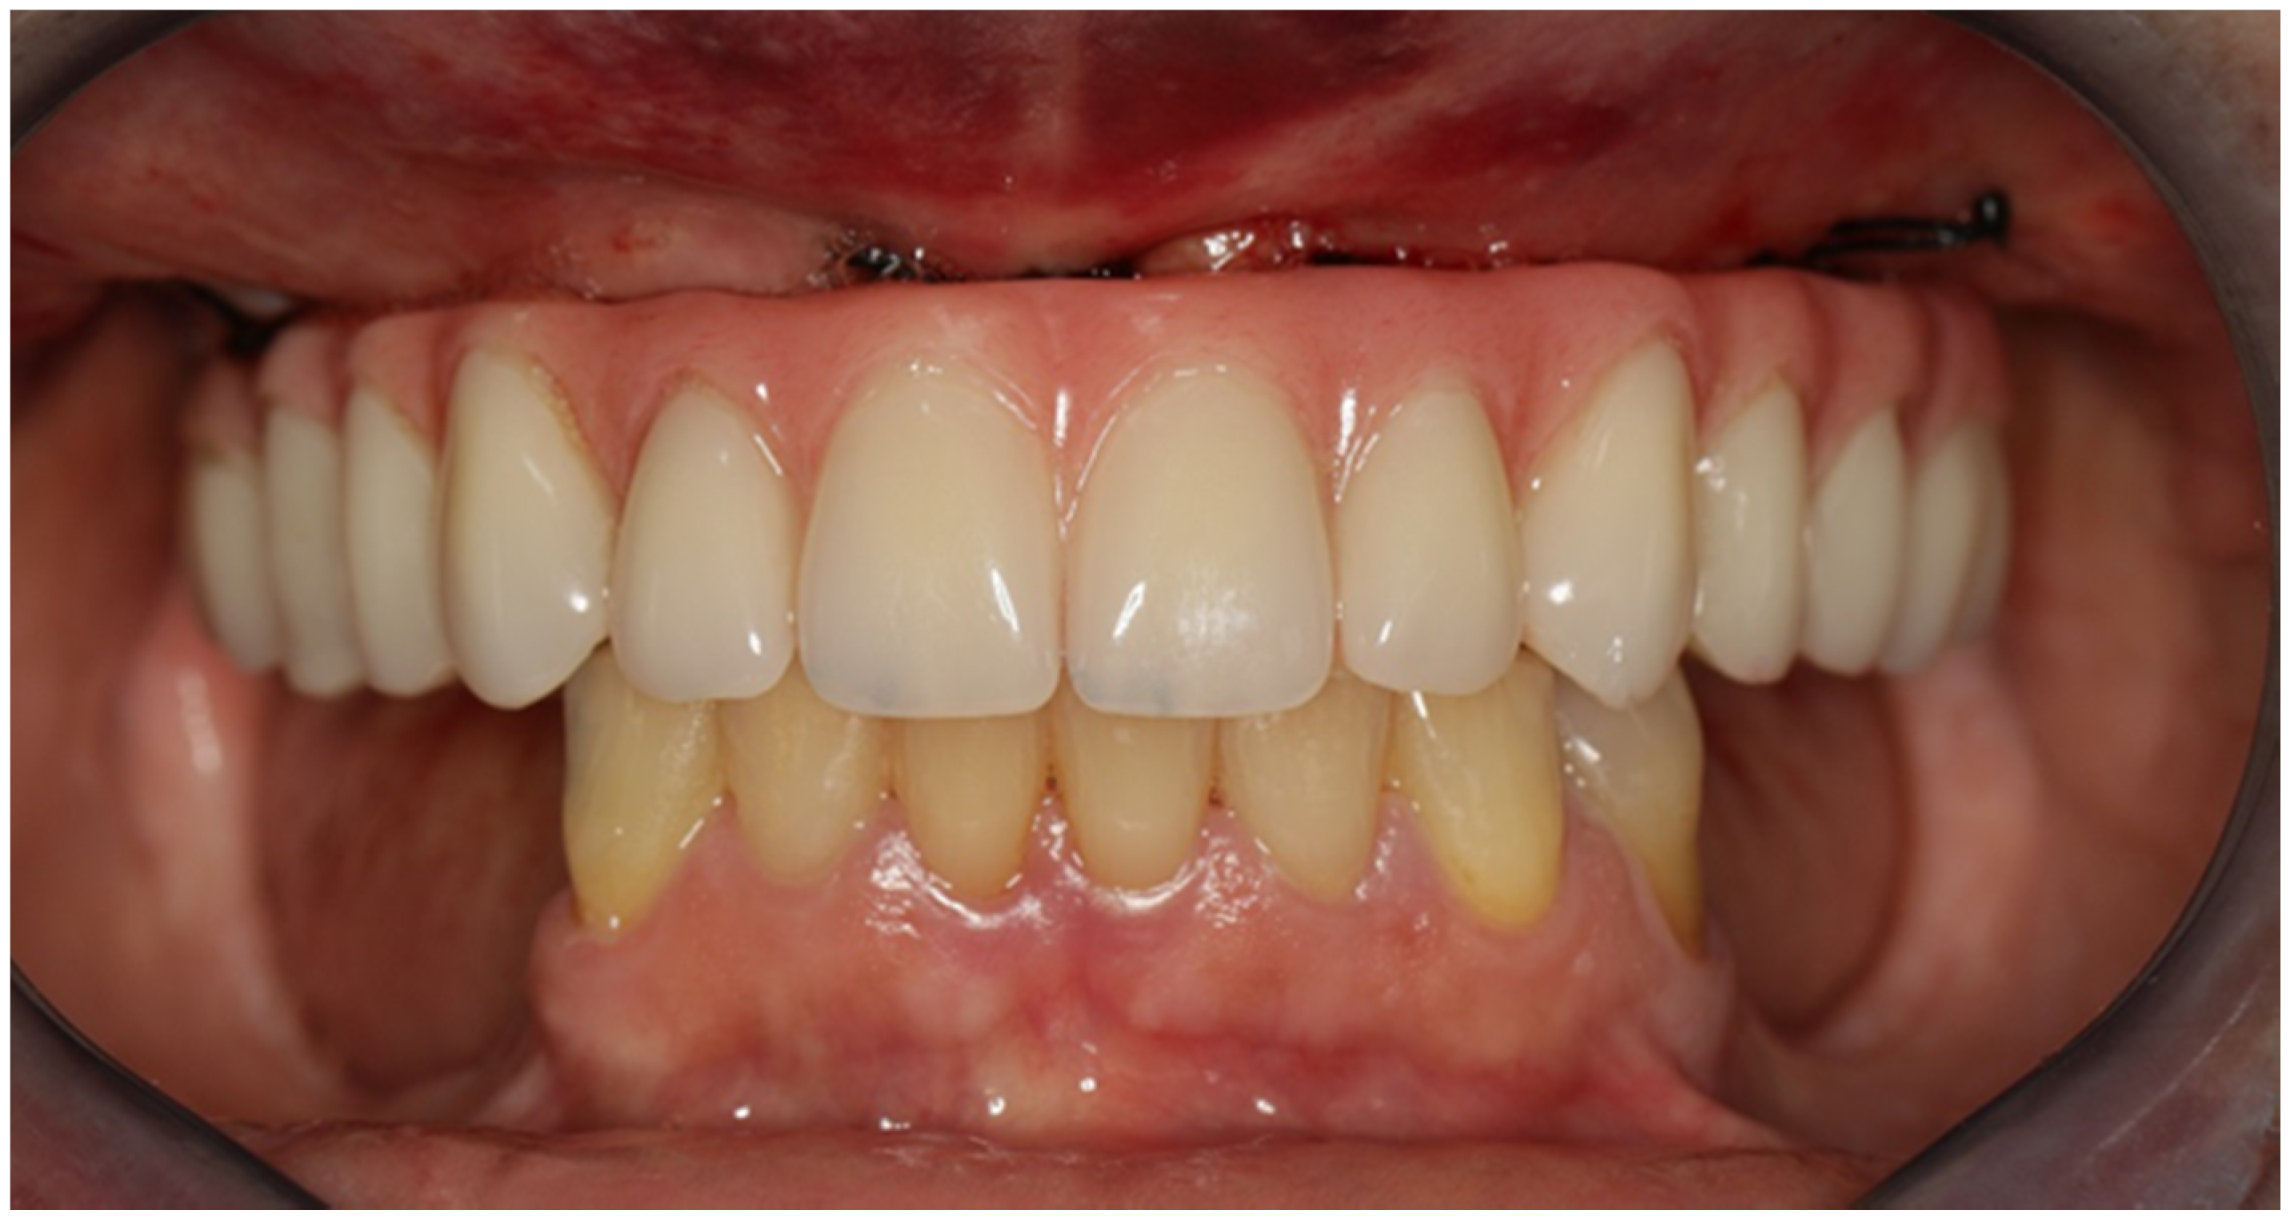

2.1. Patient 1